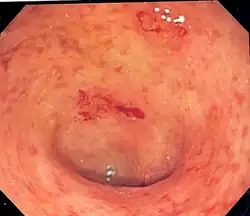

Endoscopic image of a colon affected by ulcerative colitis. The internal surface of the colon is blotchy and broken in places. Mild-moderate disease.

Endoscopic image of ulcerative colitis affecting the left side of the colon. The image shows confluent superficial ulceration and loss of mucosal architecture. Crohn's disease may be similar in appearance, a fact that can make diagnosing UC a challenge.

The best test for the diagnosis of ulcerative colitis remains endoscopy, which is the examination of the internal surface of the bowel using a flexible camera. Initially, a flexible sigmoidoscopy may be completed to establish the diagnosis.[73] The physician may elect to limit the extent of the initial exam if severe colitis is encountered to minimize the risk of perforation of the colon. However, a complete colonoscopy with entry into the terminal ileum should be performed to rule out Crohn's disease and assess the extent and severity of the disease.[73] Endoscopic findings in ulcerative colitis include: erythema (redness of the mucosa), friability of the mucosa, superficial ulceration, and loss of the vascular appearance of the colon. When present, ulcerations may be confluent. Pseudopolyps may be observed.[74]